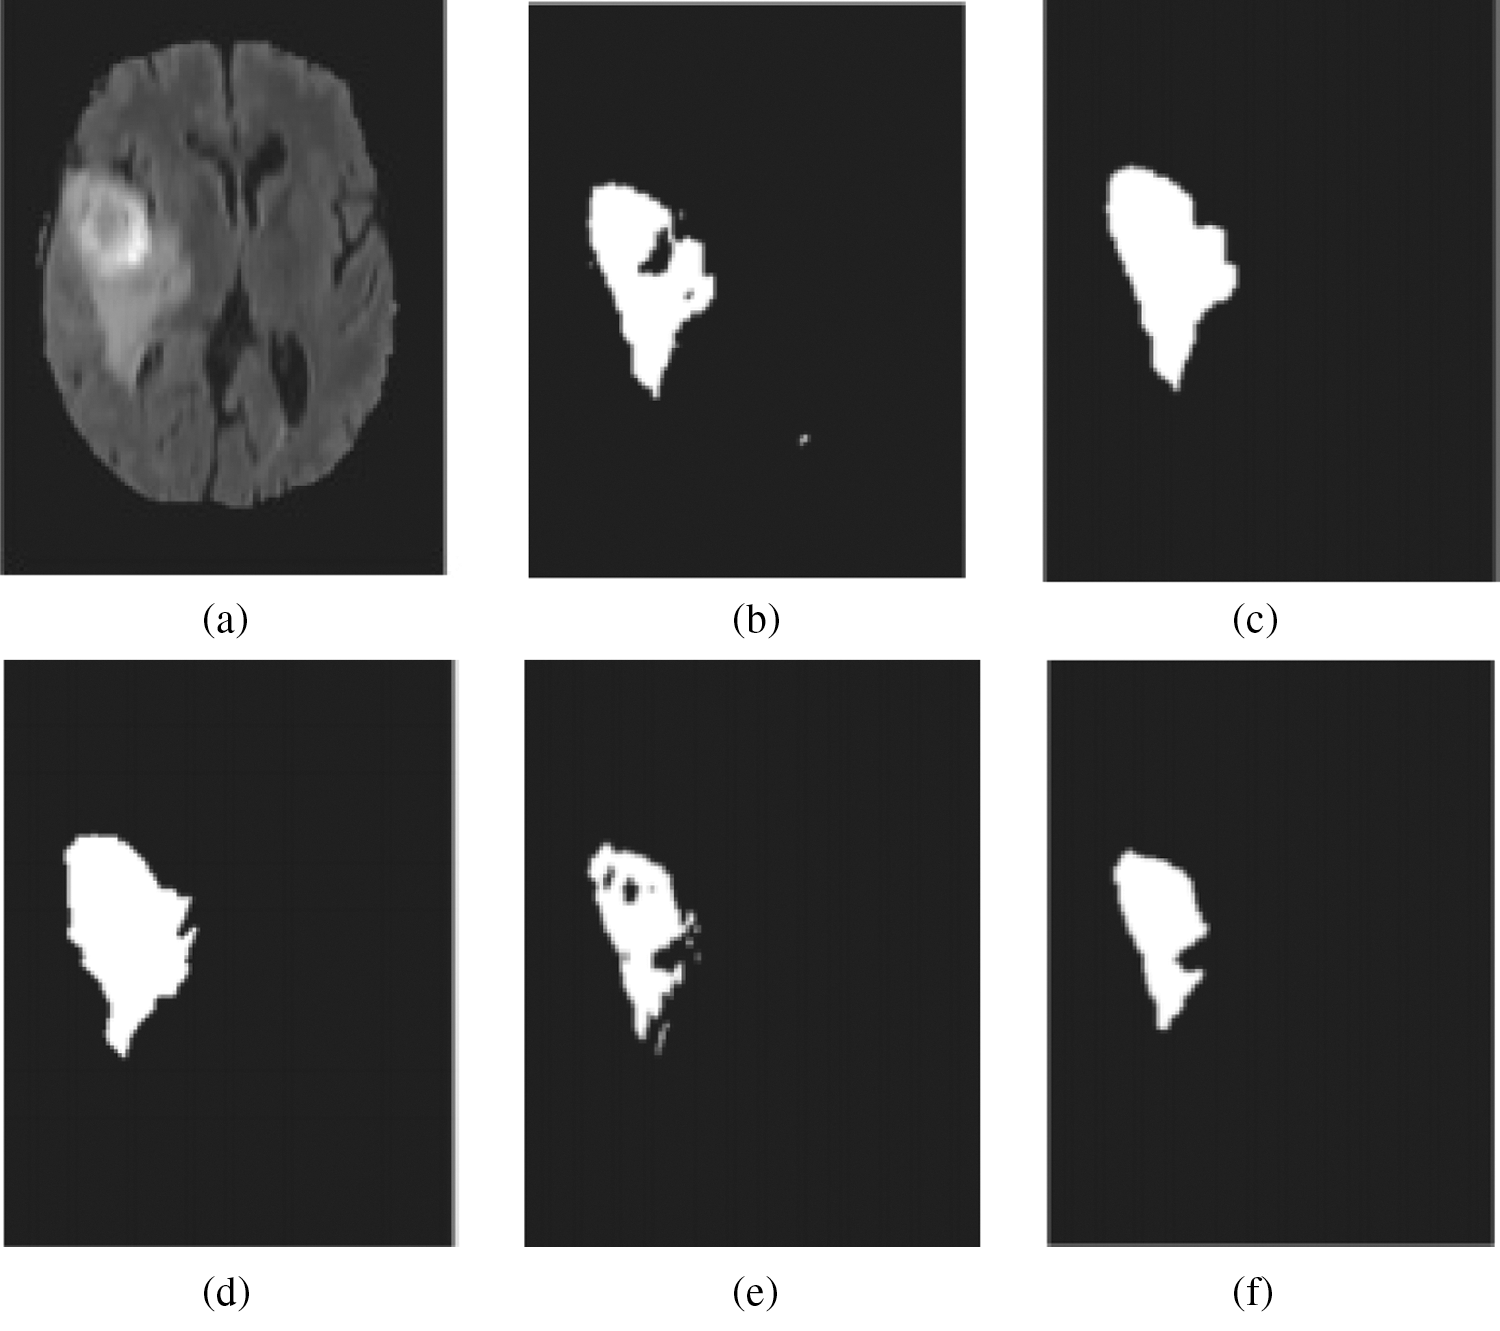

As depicted in Fig. 4c, segmented images achieved through mentioned clustering algorithm might feature small holes/over segmentation because of different factors, like intensity non-uniformity and noise.

Figure 4: Segmentation results after post processing: (a) MRI data, (b) truth of ground, (c) cancer region extorted with no post processing, (d) cancer region acquired then post processing

For post processing, Hybrid median filtering (HMF) and hole-filling can be utilized, through which the segmentation accuracy can be improved. In extracted tumor areas, the small holes are filled and a few missegmented areas filtering is done, once post-processing is completed. In Fig. 4d, the segmentation algorithm’s results are depicted, which is obtained after post processing. Besides, the original MR image is presented in Fig. 4a, and ground truth image is depicted in Fig. 4b.

Figure 5: Generation of two unstable outcomes from Intuitionist Possibilistic Fuzzy Clustering (IPFC) (a) MRI data (b) cancer area extorted from initial outcome (c) cancer area then post processing extorted from initial outcome (d) image with ground truth (e) cancer area extorted from next outcome (f) cancer area then post processing extorted from next outcome

In this work, application of Intuitionist Possibilistic Fuzzy Clustering (IPFC) is proposed to accomplish the deterministic initialization task, through which the segmentation algorithm’s stability is greatly improved. In addition, empirical findings also reveal the optimal stability of the proposed approach is referred in Fig. 5.